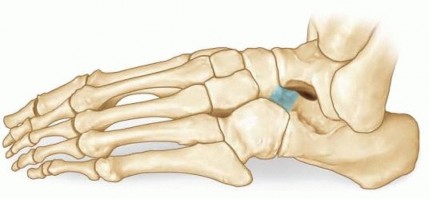

Resection of Calcaneonavicular Coalition DEFINITION A calcaneonavicular coalition is an abnormal connection b…